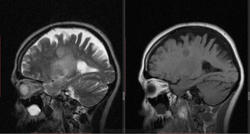

Женьщина 35 лет. В направлении гемипарез слева, дифдиагноз между образованием, инсультом и энцефалитом. Со слов болеет около 3 недель. Я такой картины ранее не встречал, склоняюсь к образованию.

Мне кажется энцефалит. Диффузию делали? Контраст? Что с анализами?

Глиальные изменения+ масс-эффект.Присоединяюсь к nnemo по поводу  проведения контрастирования и необходимости DWI. Еще  клиника и динамика в помощь.

диффузия позволит с высокой степени вероятности исключить ОНМК, останется DDx между опухолевым и воспалительным процессом. При воспалительном процессе должна быть соответствующая клиника, анамнез и анализы...

ну и конечно, если нет возможности контрастировать -  динамика процесса